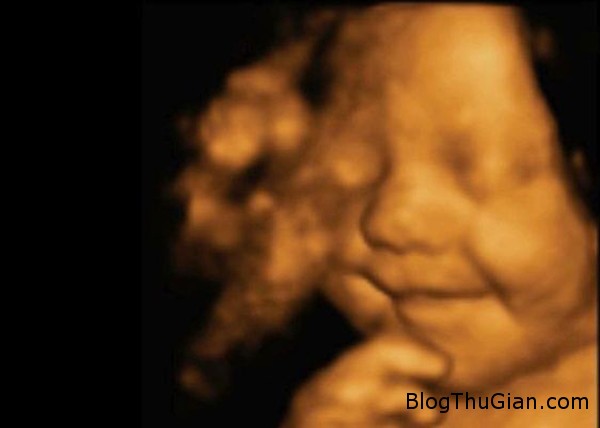

Bé Leo mỉm cười trong bụng mẹ lúc 31 tuần tuổi. Ảnh: MEN

Chị Amy Cregg cho biết lần đầu tiên nhìn thấy nụ cười rạng rỡ trên gương mặt bé Leo là khi chị và chồng, anh Leighton Hargraeves, đi siêu âm thai mốc 31 tuần. “Leighton và tôi đều thực sự bị sốc. Thậm chí người siêu âm cho tôi cũng rất kinh ngạc”, Amy, nhân viên hỗ trợ phục hồi chức năng, nói.

Bà Jadwat, Giám đốc phòng khám BabyBond, nơi Amy đến siêu âm 4D hồi tháng 5, nói: “Nhân viên của chúng tôi rất bất ngờ khi nhìn thấy đứa bé cười trong bụng mẹ suốt lần siêu âm đó. Tôi nghĩ chúng ta có thể khẳng định đây là đứa trẻ hay cười nhất từ trước tới nay”.